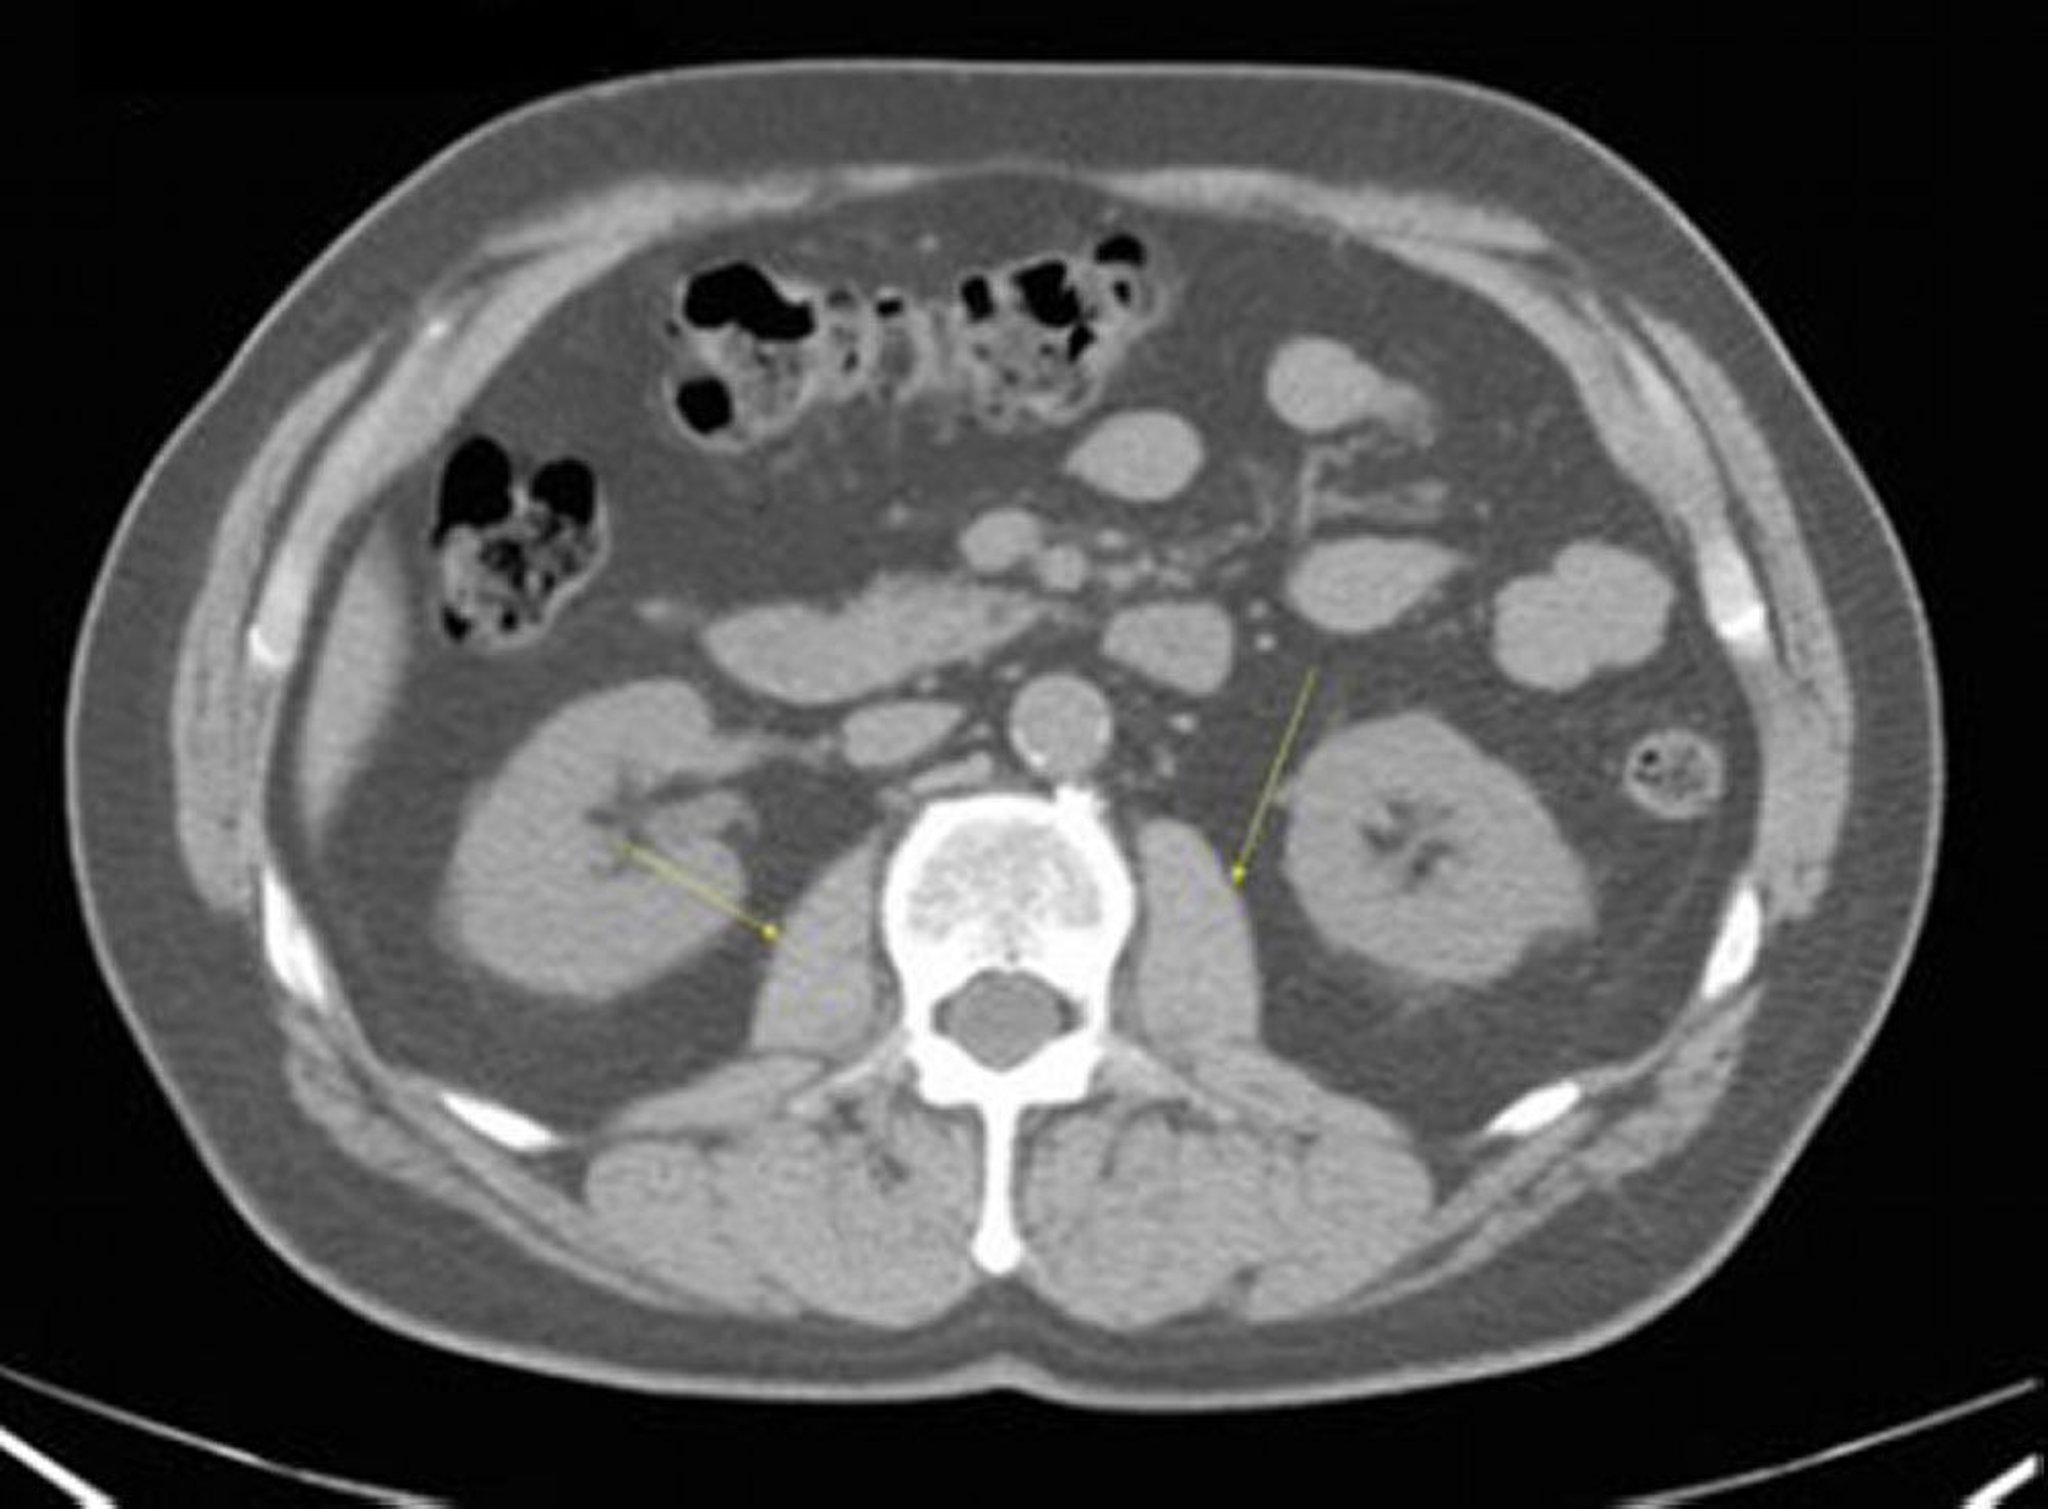

TC senza contrasto dell'addome e della pelvi che mostra un'anatomia normale (Slide 16)

Questa immagine mostra i muscoli psoas (frecce).